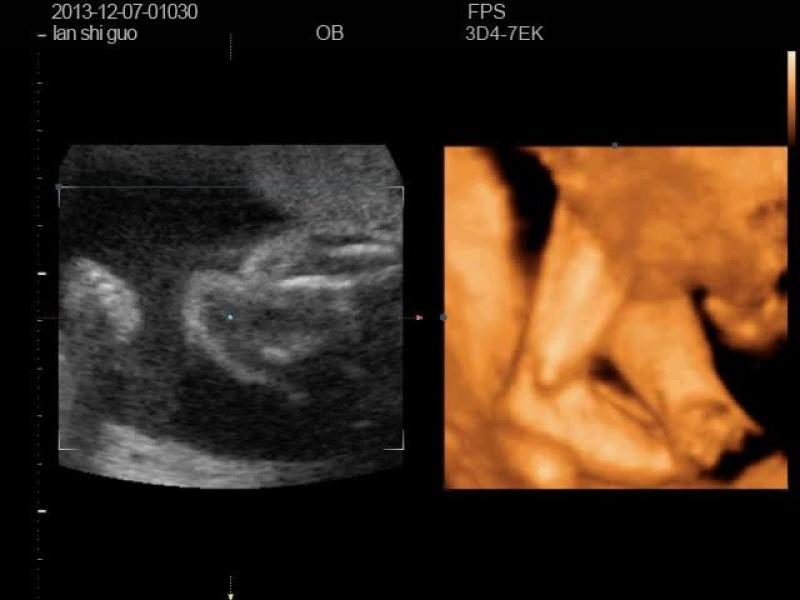

我前两天照的四维彩超,看着宝宝脚好别扭啊,哪位专家帮我看看,是不是有问题

这个是很难看出生下来后又没有问题的因为他还在长有可能是他就是这样的